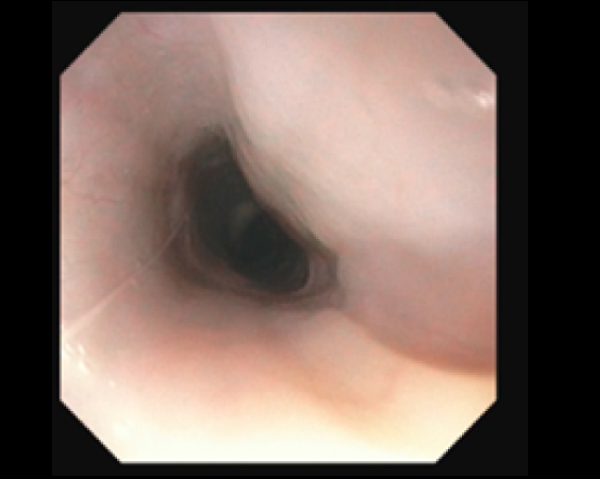

拡張後の鼻咽頭部